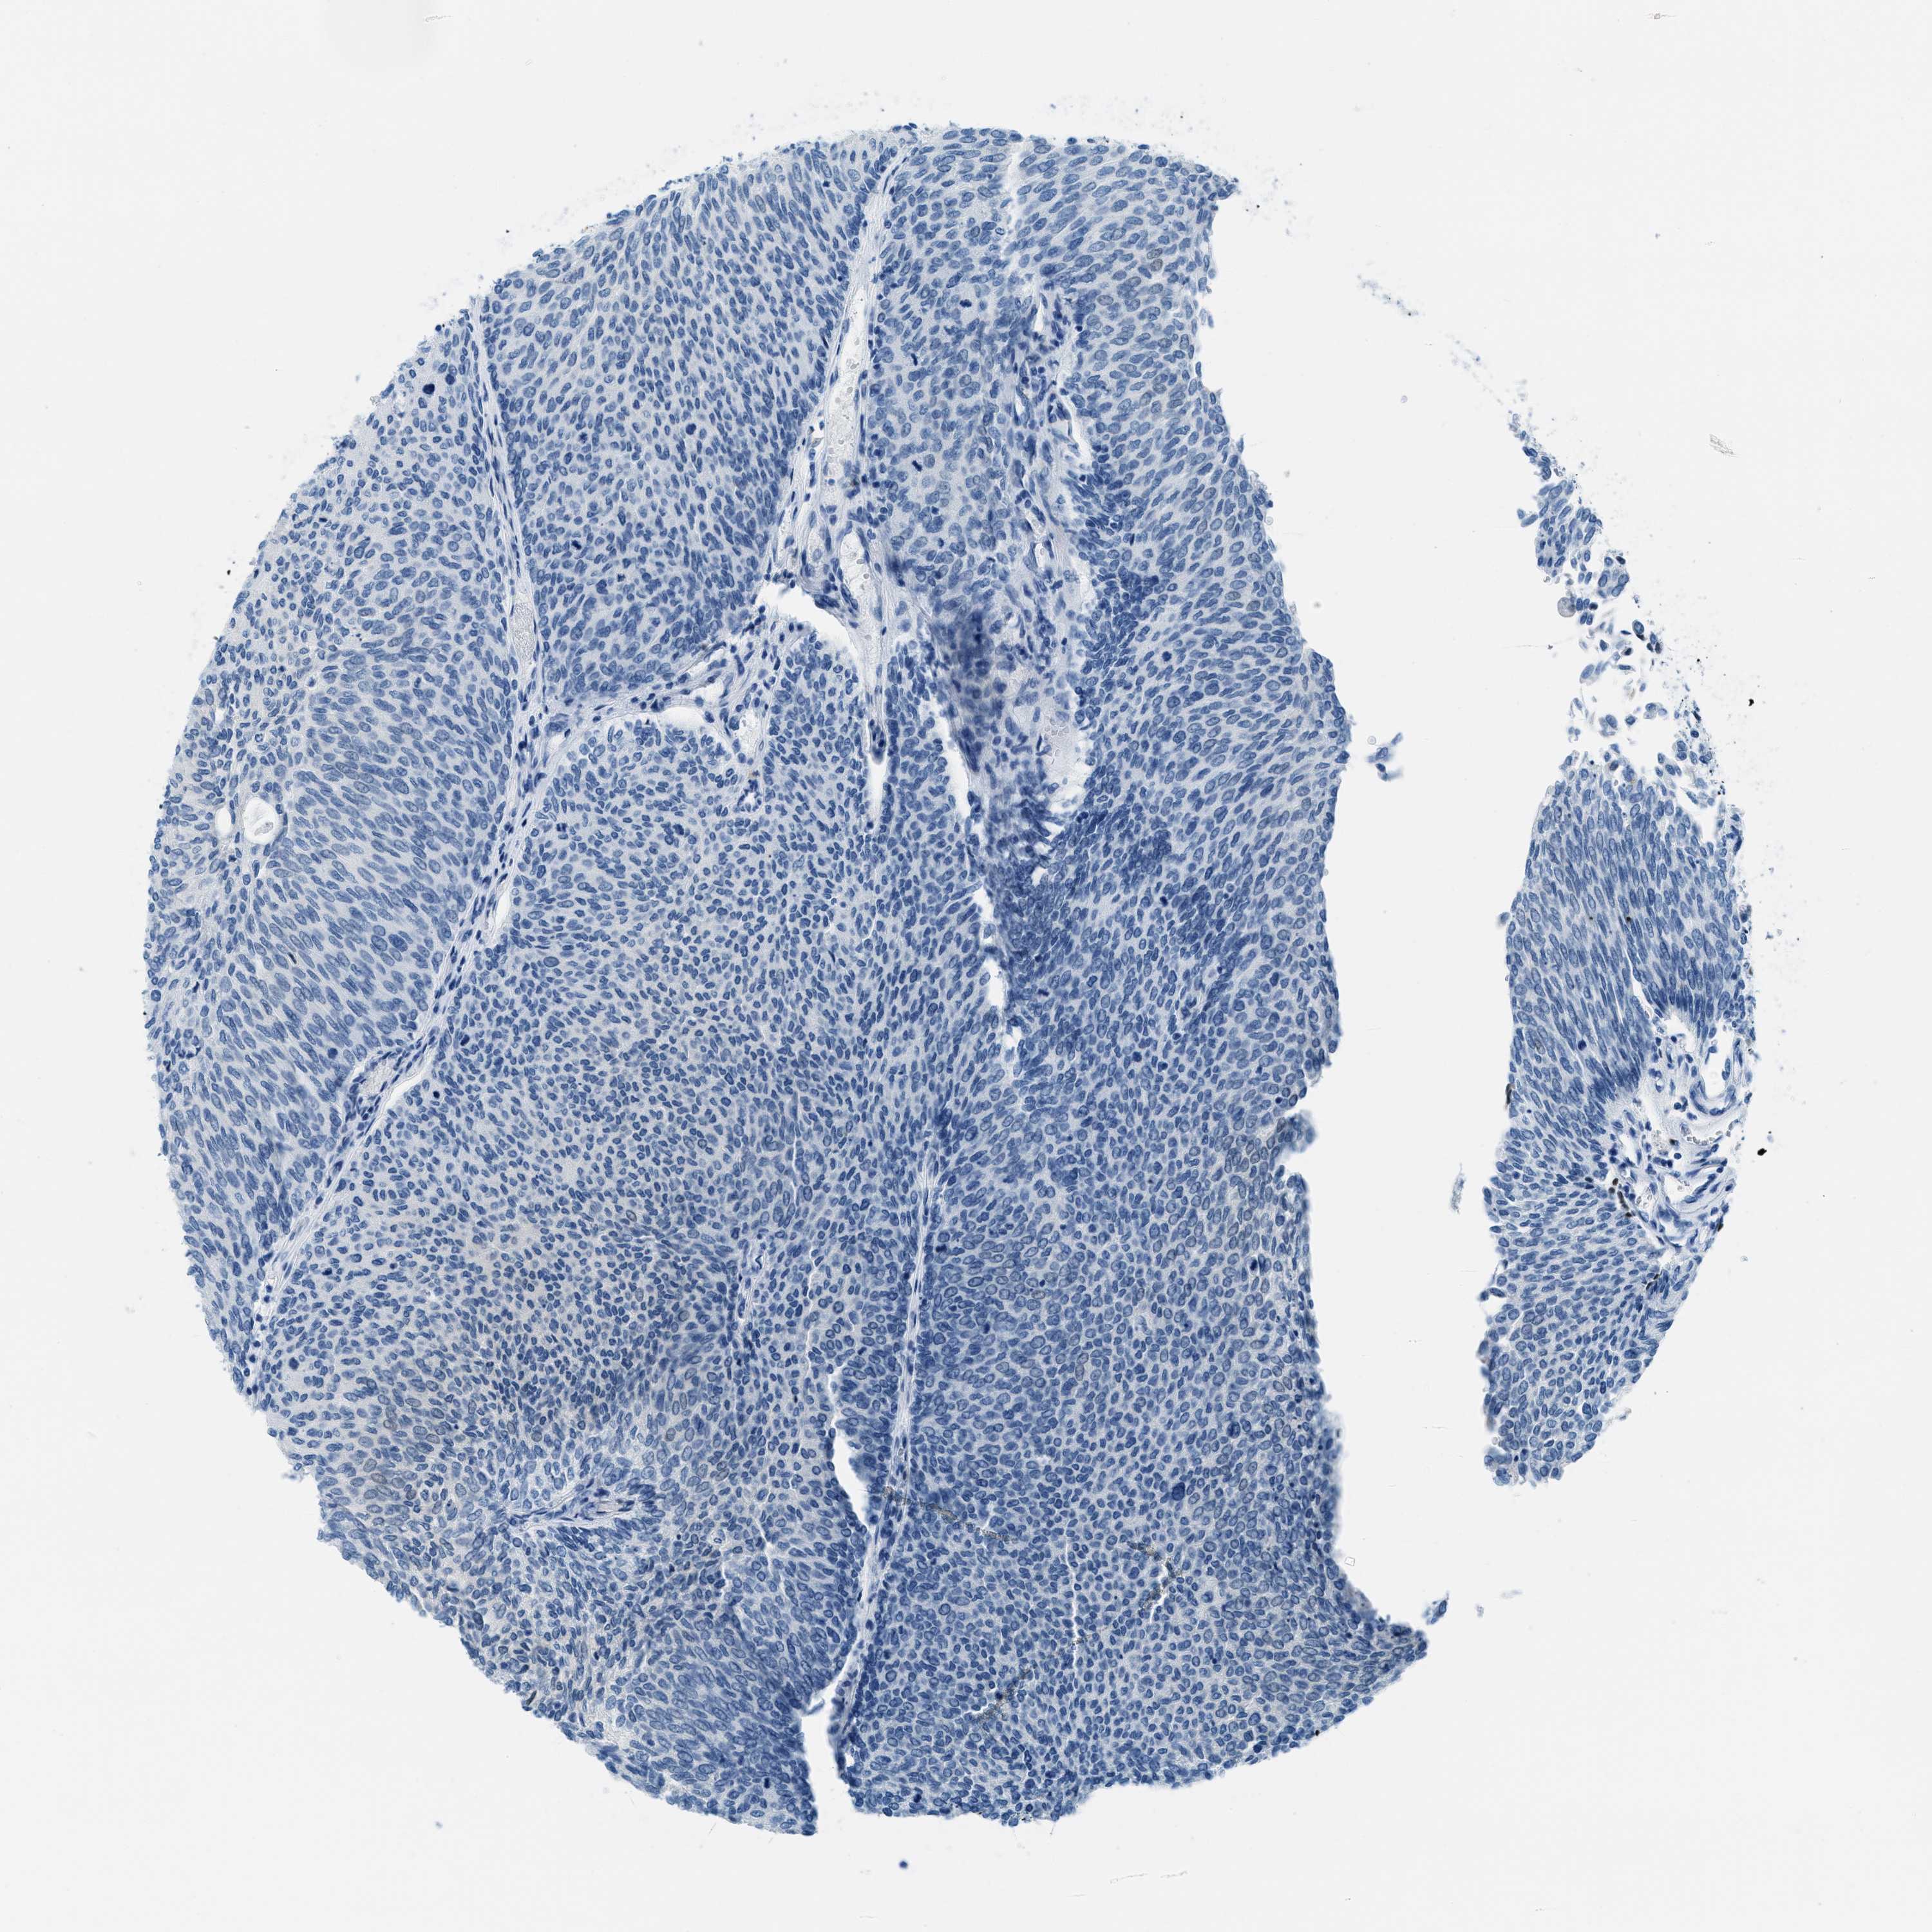

UROTHELIAL CANCER - Protein expressioni

A mouse-over function shows sample information and annotation data. Click on an image to view it in a full screen mode. Samples can be filtered based on level of antibody staining by selecting one or several of the following categories: high, medium, low and not detected. The assay and annotation is described here.

Note that samples used for immunohistochemistry by the Human Protein Atlas do not correspond to samples in the TCGA dataset.

Antibody stainingi

Antibody staining in the annotated cell types in the current human tissue is reported as not detected, low, medium, or high, based on conventional immunohistochemistry profiling in selected tissues. This score is based on the combination of the staining intensity and fraction of stained cells.

Each image is clickable and will lead to virtual microscopy that enables deeper exploration of all samples and also displays staining intensity scores, fraction scores and subcellular localization as well as patient and tissue information for each sample.

Antibody HPA015236

Staining

High

Medium

Low

Not detected

Intensity

Strong

Moderate

Weak

Negative

Quantity

>75%

75%-25%

<25%

None

Location

Urothelial carcinoma, Low grade

Urothelial carcinoma, High grade